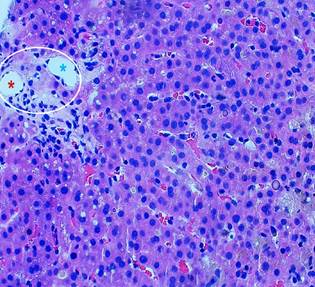

Figure 1 The histological section shows hepatic parenchyma with a portal space (circle), where portal vessels (artery and vein) are identified but no bile duct is observed (*red: artery, *blue: vein).

Leptospira infection was ruled out (negative IgM), and blood smear testing excluded hemoparasite-related diseases. Endoscopic studies showed no significant findings except for antral hyperemic gastritis. An initial abdominal ultrasound detected hepatomegaly without other abnormalities. Subsequent magnetic resonance cholangiography ruled out choledocholithiasis or biliary duct dilation. Finally, a percutaneous liver biopsy revealed marked cholestasis and loss of bile ducts in portal triads. Immunohistochemical staining confirmed focal duct destruction in portal triads (Figures 1, 2, and 3).

Current diagnostic criteria require: biochemical cholestasis, normal endoscopic studies excluding inflammatory bowel disease, absent antimitochondrial antibodies, no granulomatous cholangitis, absent histiocytosis X, no suppurative neutrophilic cholangitis, no lymphoma or neoplasia on liver biopsy, and histopathological confirmation of ductopenia. The latter requires loss of ≥50% of septal/interlobular bile ducts in a sample containing ≥20 portal tracts, without granulomatous cholangitis or florid ductal injury1,2,6-9 (Figures 1 and 3).